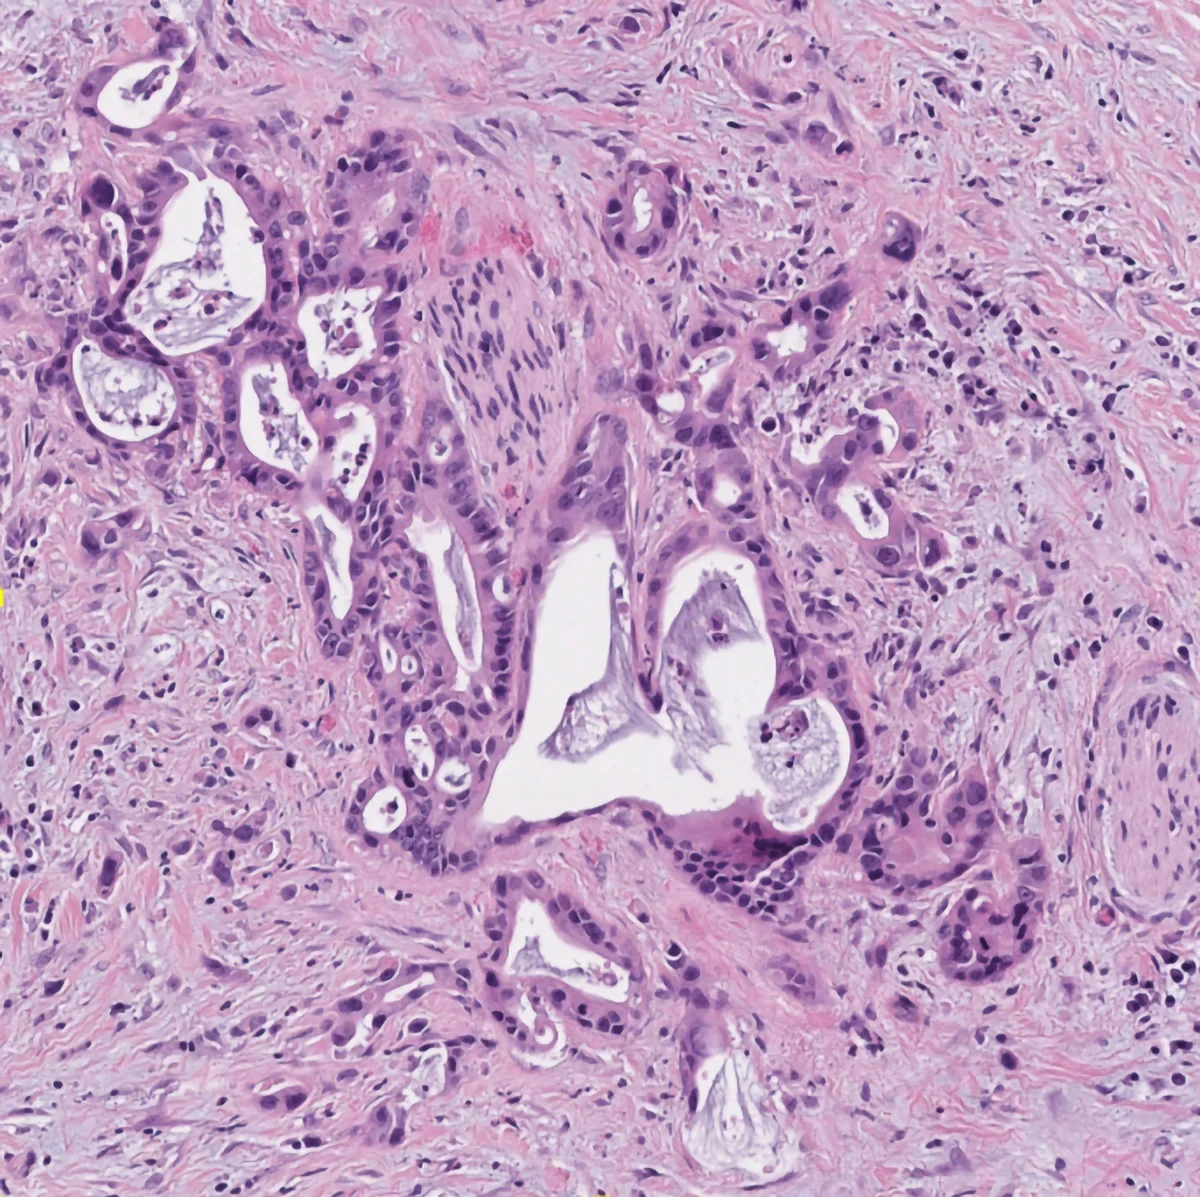

A major focus in the lab lies on pancreatic ductal adenocarcinoma (PDAC), which remains one of the most challenging cancers to treat. PDAC is a notoriously heterogeneous cancer type, characterized by a complex tumor microenvironment (TME) which has complicated mechanistic and preclinical studies for decades. This heterogeneity was long thought to be the result of random cell changes representative of global tumor disorganization. Based on our own findings and a growing body of evidence in the literature, we are convinced that heterogeneity in solid tumors is not at all random but a critical foundation of malignant tissue function and adaptive behavior. In fact, solid tumors exhibit a considerable level of functional self-organization that we have barely appreciated. For instance, in PDAC, we find distinct spatial programs that are vastly distinct from each other, yet, highly conserved between different patients and disease sites. Their intratumoral co-existence instigates massive spatial heterogeneity yet, this heterogeneity is a well-definable function of few, fundamental tissue organizational mechanisms. In other words, despite their famous heterogeneity, PDAC tissues facto self-organize into relatively few states of functional relevance. Ongoing efforts in the lab are to understand whether other solid tumor types (lung, kidney, bladder) also utilize such spatial self-organizational programs, what their organ-specific tumor relevant functions are, and how we can diagnostically access this information to aid clinical decision making.

Multimodal Tissue Phenotyping

Histopathology remains a bedrock of our approaches and subsequent analyses. Histology reflects tissue organization and we have capitalized on this conserved form-and-function relationship in many of our analytical approaches. Beyond traditional histopathology we are now increasingly using deep learning models to extract relevant histotypes and resultant larger scale topologies from H&Es. For subsequent profiling of defined histological phenotypes, we employ various histology-guided spatial profiling techniques such as Laser Capture Microdissection coupled to multiOMICs, CODEX and Imaging Mass Cytometry. Our wide analytical portfolio is enabled through phenomenal, long-standing collaborators active in technology development who continue to make their newest techniques available to our research questions.